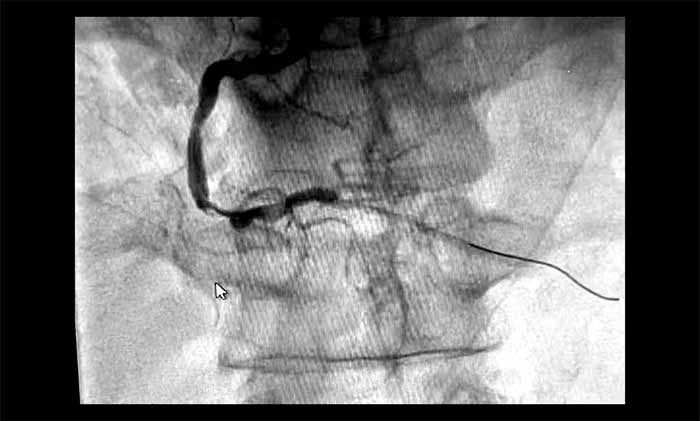

▲ 术前,RCA中段严重狭窄(约95%)伴血栓

1月28日,姜朝晖博士团队为患者行冠状动脉球囊扩张及支架植入。术中,行多角度造影提示RCA中段严重狭窄近95%,并伴有血栓。通过及时介入,开通闭塞血管,恢复了心肌供血。